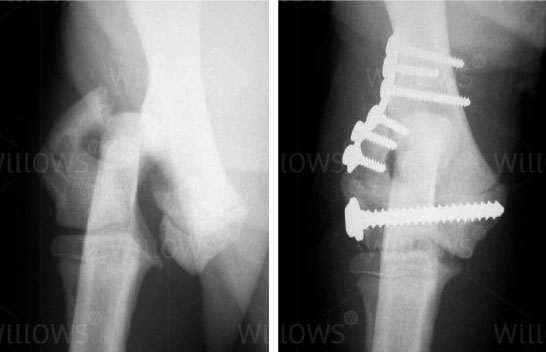

Fig 2: Severe fracture of the humeral condyle repaired with two plates and multiple screws